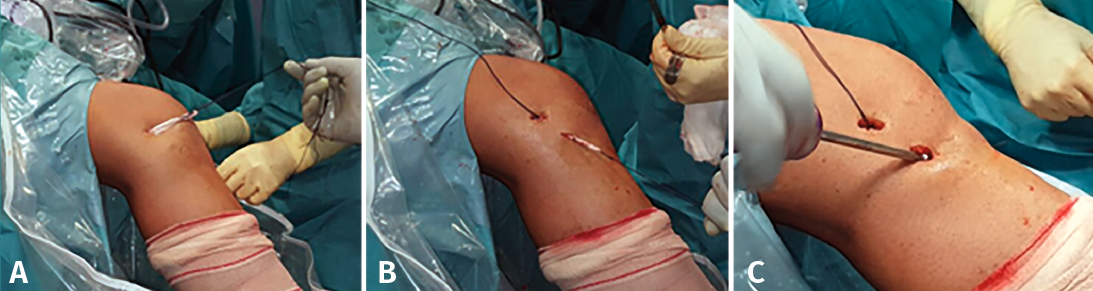

En cuanto al injerto utilizado para la reconstrucción del complejo AL, los más populares son la fascia lata para la TEL(61,68,71)(Figura 4) y los tendones isquiotibiales para la reconstrucción del LAL(66,67)(Figura 5), aunque estos también han sido utilizados para la TEL(72). Asimismo, también se han utilizado plastias artificiales(73), injertos heterólogos(74) y refuerzos con cinta de sutura(75). Actualmente, no hay ningún ensayo clínico que compare ambas técnicas.

Figura 5. Plastia del ligamento anterolateral con tendones isquiotibiales sobrantes de la plastia del ligamento cruzado anterior (LCA) según la técnica descrita por Espejo-Baena et al.(67). A: injerto insertado en el cóndilo femoral externo; B: paso percutáneo de la plastia hasta su inserción tibial; C: fijación en la cara anterolateral de la tibia con tornillo interferencial.